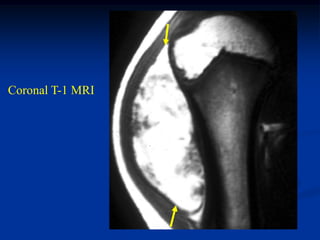

Case #1202

80 year male with

pleomorphic liposarcoma

Sagittal T-1 MRI

Sagittal T-2 MRI

Case #1202 80 yearmale with pleomorphic liposarcoma Sagittal T-1 MRI

• 255.